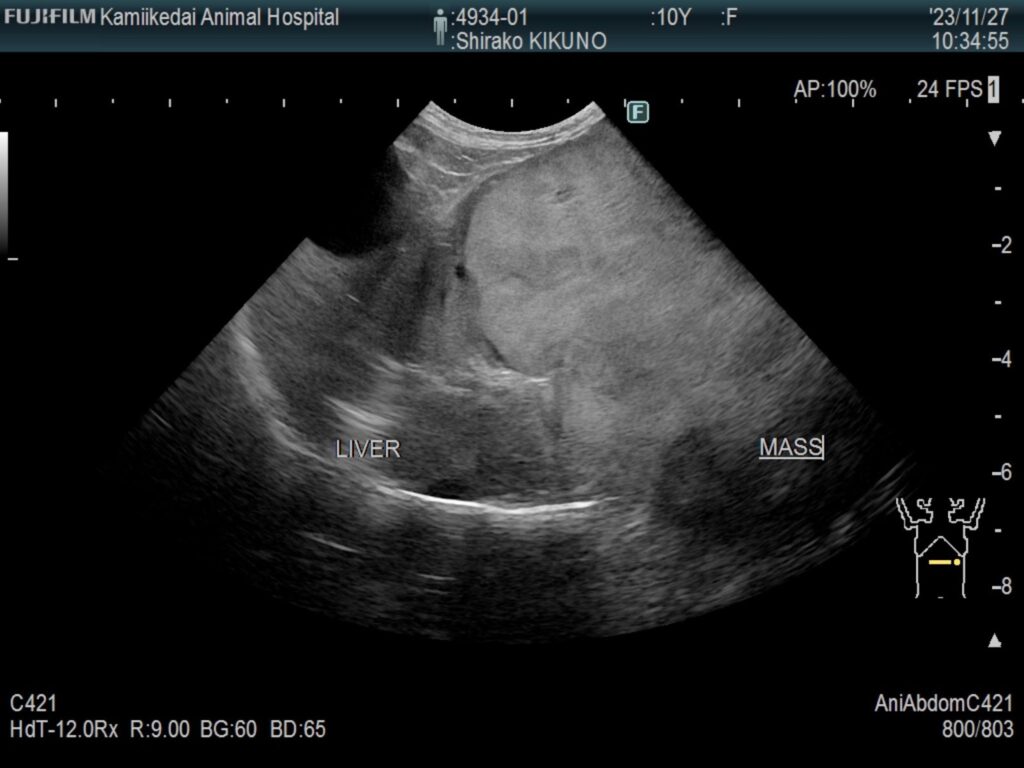

他院での健康診断で肝臓の腫瘍が見つかり、当院に来院された症例をご紹介します。

エコー検査にて肝臓の左葉に腫瘍を認め、血液検査などで手術可能な一般状態であると判断し、CT検査にて腫瘍の正確な位置を特定しました。

▼初診時の肝臓エコー画像

CT検査の所見から肝細胞癌疑いと判断し、肝臓の左区域切除を行いました。その際、手術時の出血リスクに備えて、事前に術中輸血用の採血なども行い、手術を行っています。

術後は定期的にエコー検査や血液検査を行い、術後から1年半経った今でも、元気に過ごしてくれています。